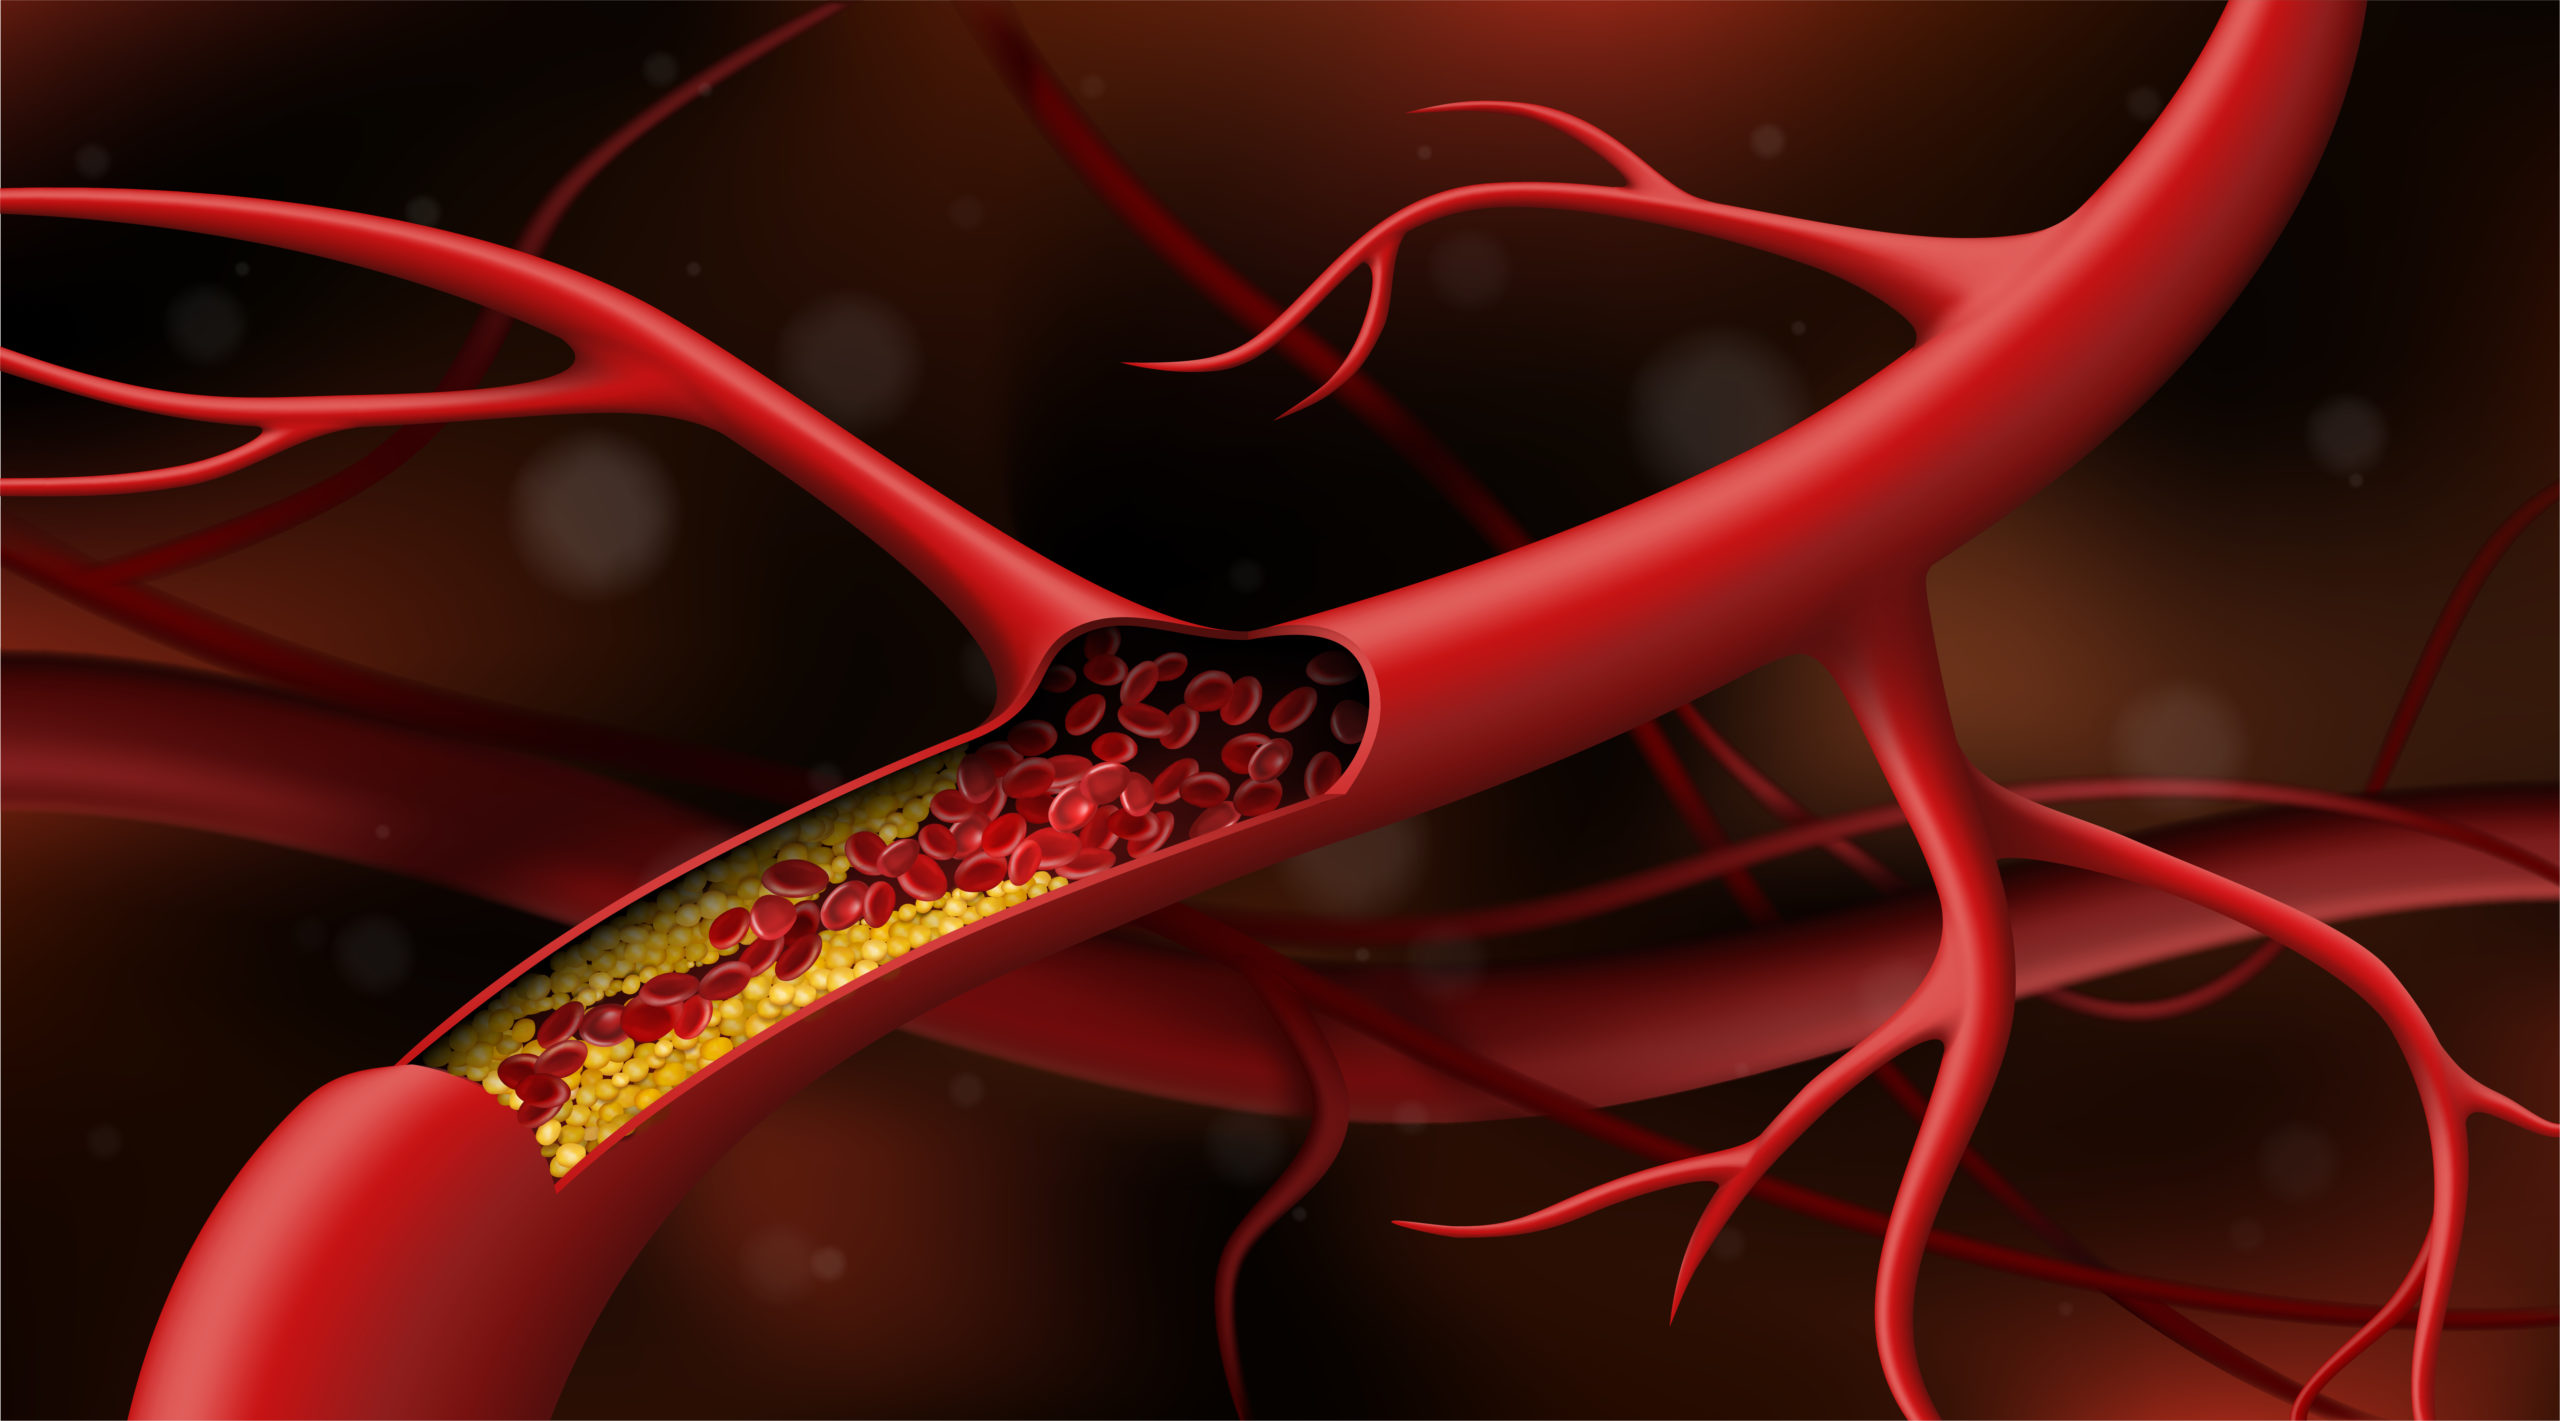

Drs. Hady Lichaa and Hayder Hashim discuss coronary microvascular dysfunction and how to manage it.